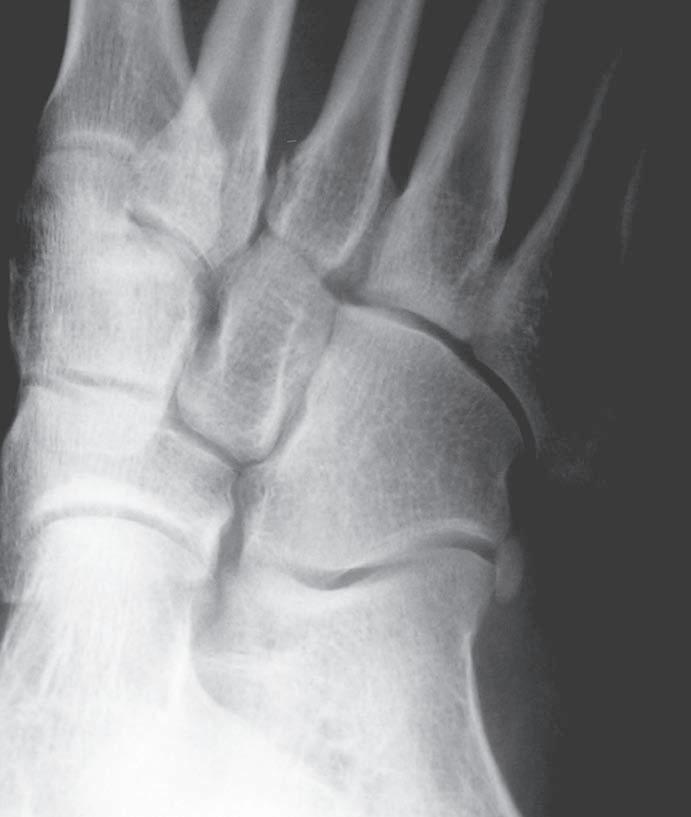

O br. 1.3 Skia g ram nohy v předozadní pro j ekci – akcesorní kůstka laterálně od k alkaneokuboidálního skloubení (os p eroneum)

Obr. 1.4 Skiagram hlezna v předozadní projekci – normální fyzární linie na distální tibii a fibule (viz šipky) u adolescenta